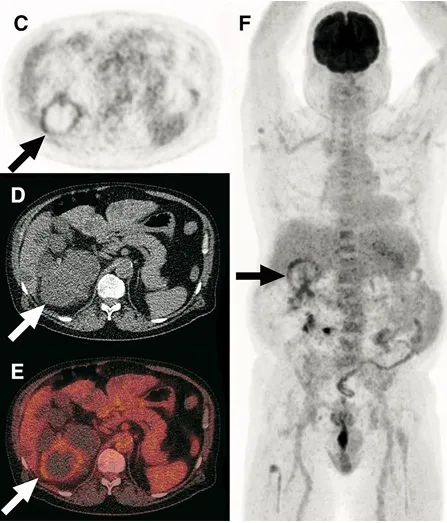

O 18F-FDG PET/CT surge como ferramenta de maior especificidade, útil para localizar o(s) cisto(s) infectado(s) e definir o alvo da punção.

📚 Na série de casos da imagem abaixo (**[link](https://link.springer.com/article/10.1007/s40336-017-0261-8)**), é possível ver como o PET/CT-FDG orienta a conduta e modifica o manejo em infecções renais e hepáticas na DRPAD.